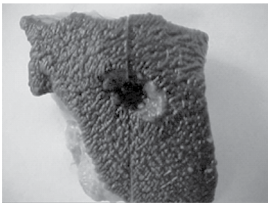

A figura seguinte mostra lesão decorrente de projétil de arma de fogo.

É correto afirmar que

É correto afirmar que